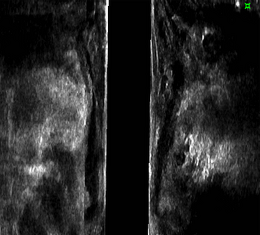

肛門超音波検査

お尻から専用の超音波装置を挿入し、肛門の筋肉や内側の壁の層構造を観察します。

主に肛門括約筋の状態や肛門周囲膿瘍(のうよう)の有無、痔瘻(じろう)の走行像などの評価に用います。